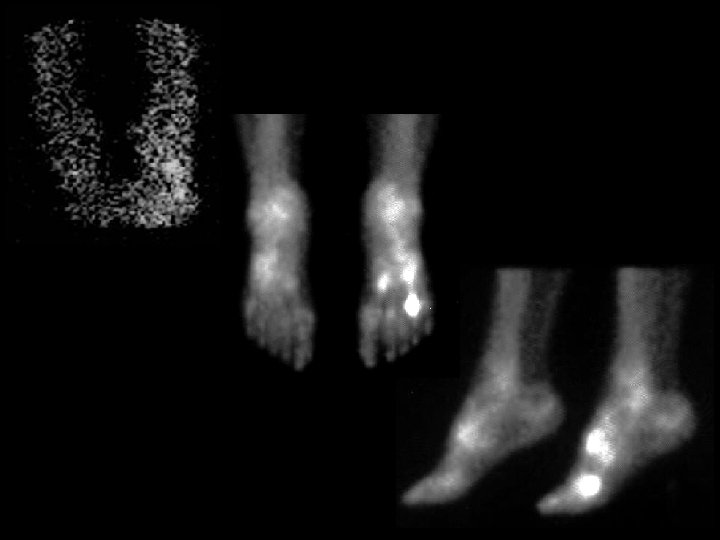

Hypertrophic osteoarthropathy • Finidings: – Linear uptake in the lower extremities, less so in the upper • ddx: – Primary: • Pachydermoperiostitis – Secondary • Pulmonary • Venous insufficiency • Thyroid acropachy • Renal osteodystrophy